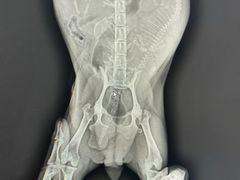

• 北京博爱动物医院有限公司

• -北京博爱动物医院有限公司